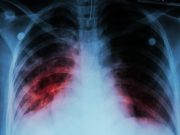

Three All-Oral Shortened Regimens Noninferior for Rifampin-Resistant TB

Noninferior efficacy seen for three all-oral regimens compared with standard therapy in intention-to-treat, per-protocol populations

Health Officials Alarmed by Tuberculosis Outbreak in Kansas

Local health officials are offering free TB testing to help control the outbreak